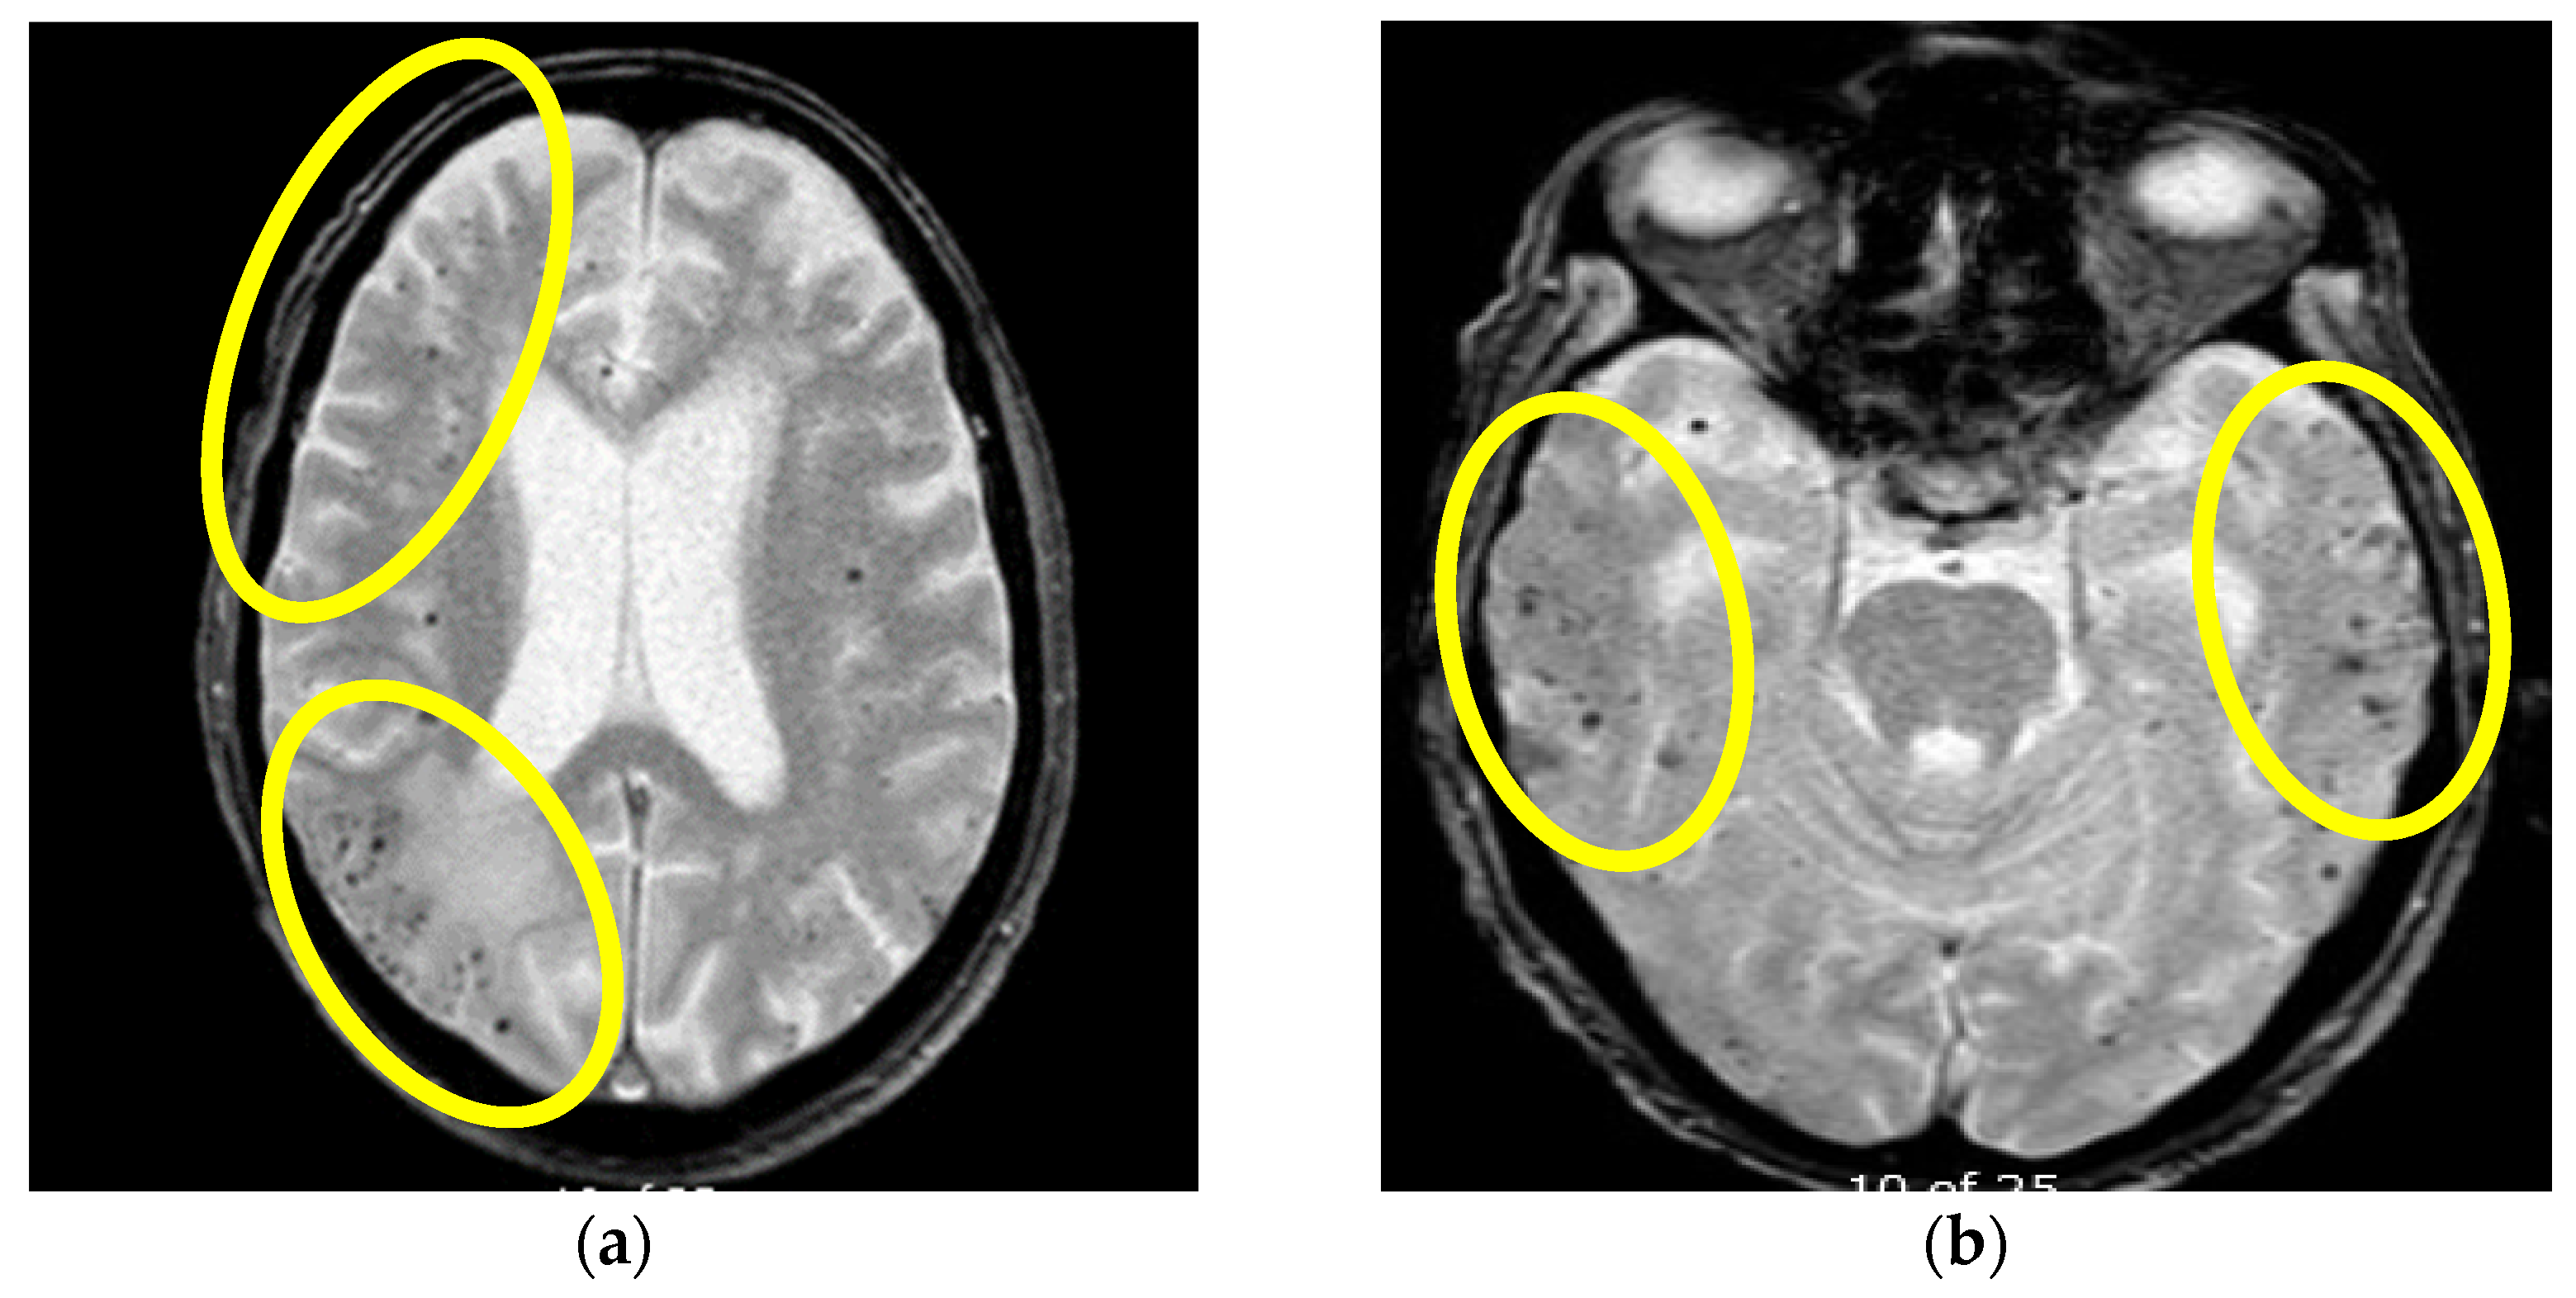

Figure 4.

Initial MR axial T2*W sequence (a) and control MRI one month after therapy initiation (b): (a) showing bilateral multiple punctiform hypointensities supratentorially, representing deposits of hemosiderin on the first MR examination, (b) showing the persistence of bilateral multiple punctiform hypointensities supratentorially. Yellow circles are showing the bilateral location of the multifocal hypointensities (Patient No. 2).

Based on these findings a diagnosis of probable CAA-rI was established. Initially, pulse methylprednisolone (1 g/daily) therapy was administered for 5 days, followed by oral prednisone (1 mg/kg), slowly tapered down during the next 3 months. During the immunosuppressive treatment, our patient had a verified septic state but was successfully treated with intravenous antibiotic therapy. The follow-up MR examination one month after treatment initiation showed mild progression of the WMH lesions with the persistence of previously noted microbleeds (Figure 3 and Figure 4). Although her neurological examination was without focal neurological deficit, the patients was still complaining about the presence of headaches and her control neuropsychological assessment was mildly improved from the initial mini-mental state examination (MMSE) 22/30 to MMSE 23/30. Thus, treatment with oral prednisone (10 mg/daily) was reintroduced. The third follow-up MR examination after six months showed resolutions of the WMH lesions (not shown), while her neuropsychological assessment was further improving.